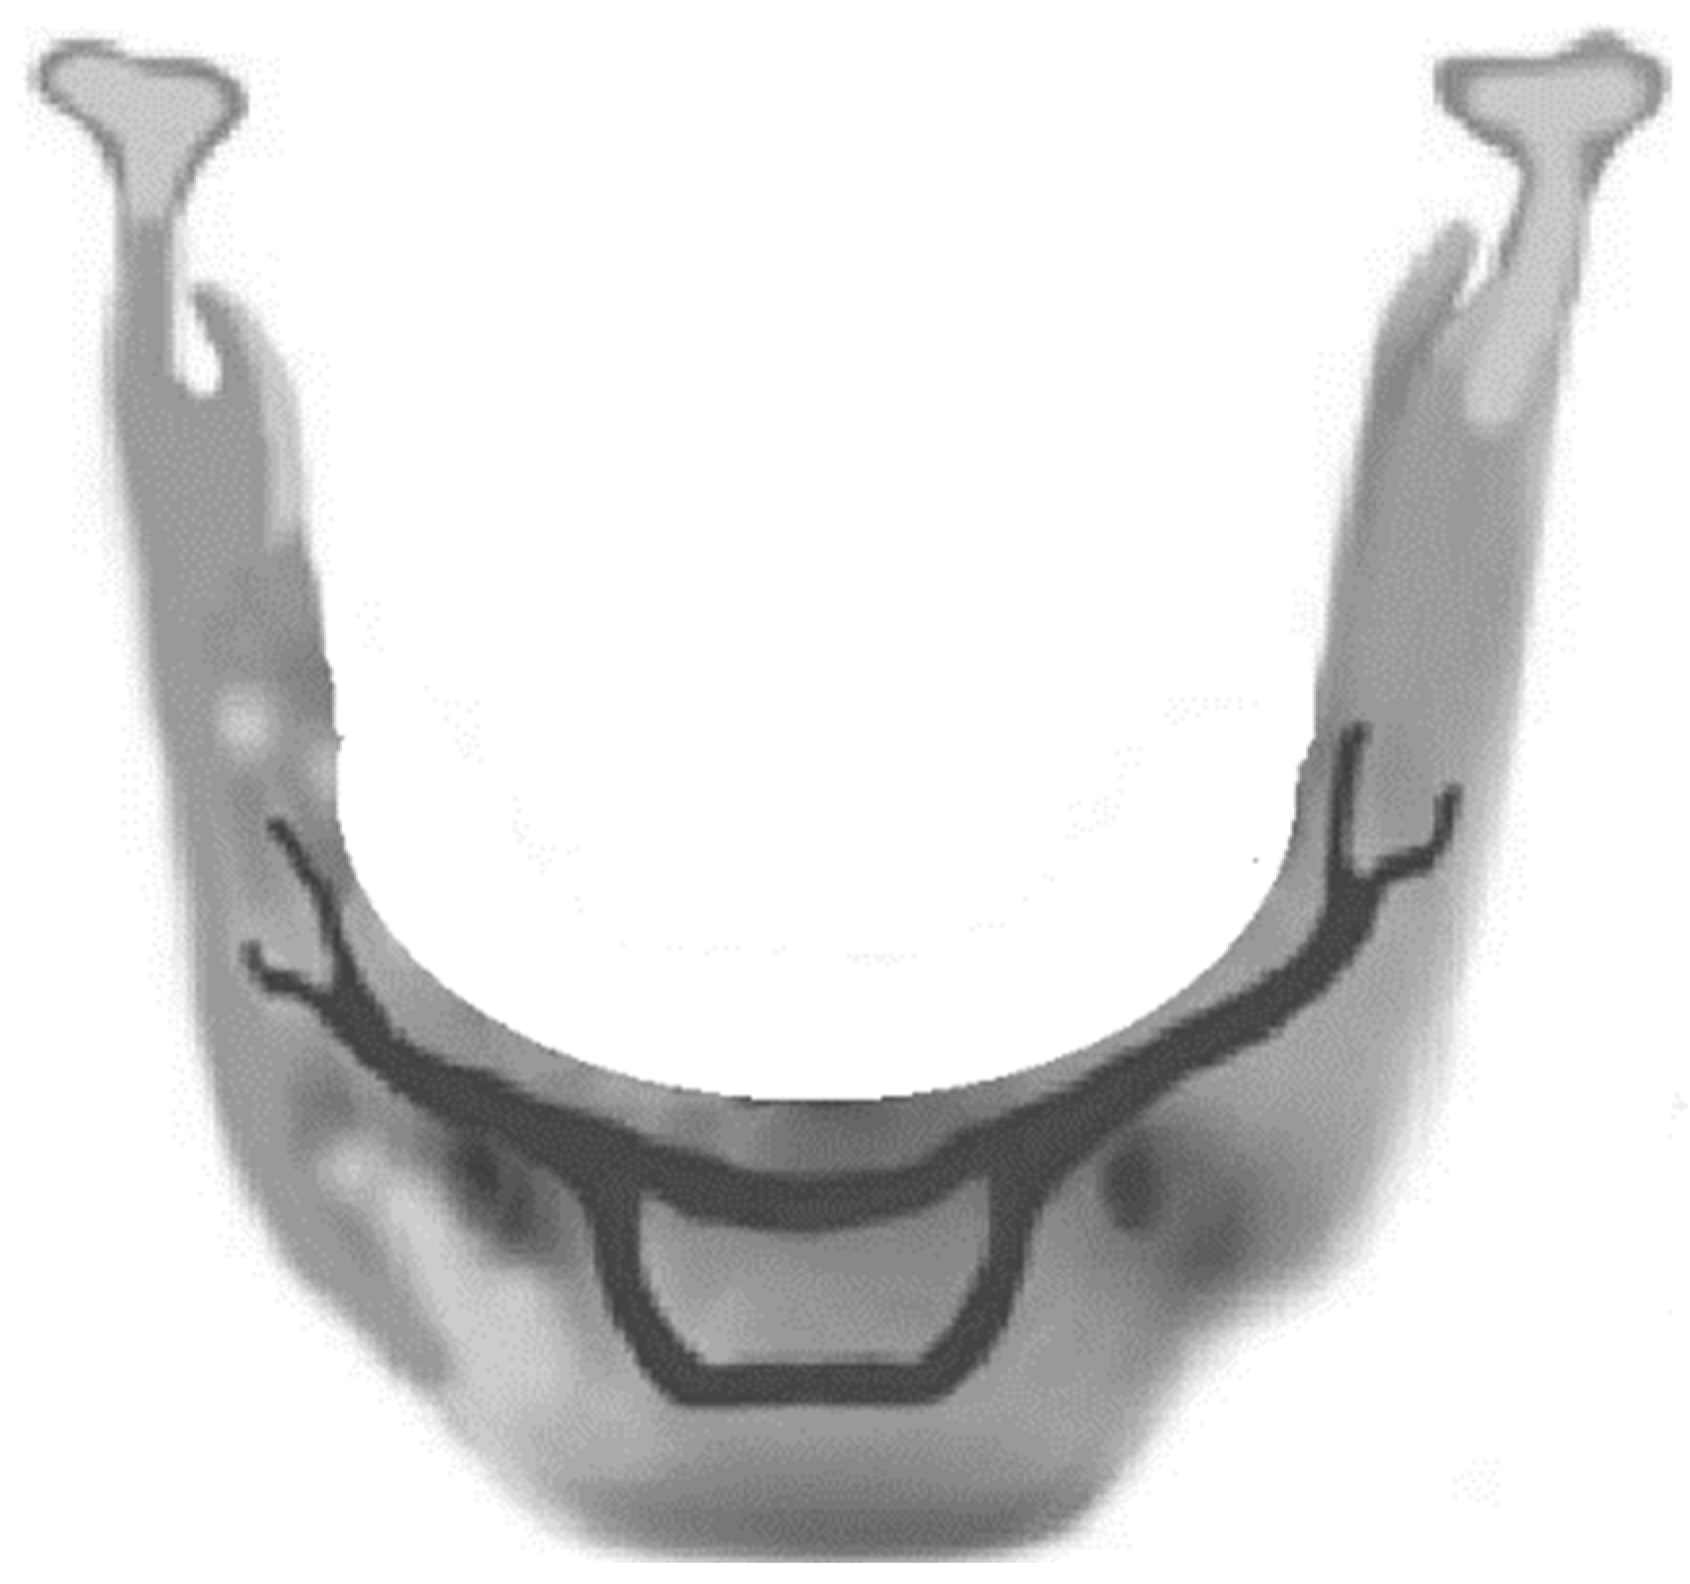

A 35-year-old male patient’s orthopantomogram is shown in Figure 1a, which is implemented as a clinical example of a symphysis fracture. The fourth author performed the surgery at Aleppo University Hospital. In this surgery, two mini-plates of I type (Figure 1b) are utilized. The mini-plates that have five holes and four screws, which were implemented using the symphysis fracture, as shown in Figure 1a. Luckily, there were no specific treatment-related complications, and the recovery time was close to three months. In order to investigate the detrimental impact brought on by the stabilization of the fracture, a three-dimensional finite element model was employed. The model is built using a panorama of a 2D picture, with an estimation of the dimensions used to provide the section in SolidWorks. Finite element analysis was conducted using Ansys Workbench. Figure 1c shows the different boundary conditions and a section illustrates the bone tissues (cortical and cancellous bone tissues). Measuring the von Mises stresses, which are thought as a sign of mandibular fractures, at the end of the healing period, is intended to achieve acceptable rigidity.

Figure 1.

(a) A 35-year-old male patient’s orthopantomogram, (b) dimensions of the mini plates in mm, and (c) finite element model with boundary conditions where the letters represent the locations of the applied forces as will be explained in Section 2.3.